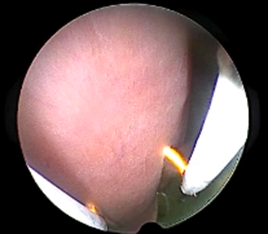

A 5mm trocar was used to create an opening, approximately in the midsection on any one of the sides of the pepper as an entry point for the resectoscope. The model was then placed on a suitable stand, placed in a reservoir tray to collect the fluid spill. This was then placed at a convenient height with the monitor placed at a location mimicking the ergonomics of actual surgery. This model was provided at each station. The participants were provided resectoscopes with a bipolar loop electrode, connected to the electrosurgical generator set to the same parameters as actual surgery and given instructions and guidance on its assembly. The trainers emphasized the importance of correct surgical techniques like placing the loop behind the myoma and activating the energy only as the loop moved towards the operating surgeon, never away from him/her. resectoscope with a bipolar loop electrode was then used to practice myomectomy on the animal tissue and shave off bits with the correct technique, while dealing with the problems of vision caused due to bits of tissue and bubbling (Figure 12). At the end of the session, the pepper was cut in half for the trainees to inspect the result of their practice.

Figure 12: Tissue bits and bubbling

Figure 11: Resectoscopic Surgery